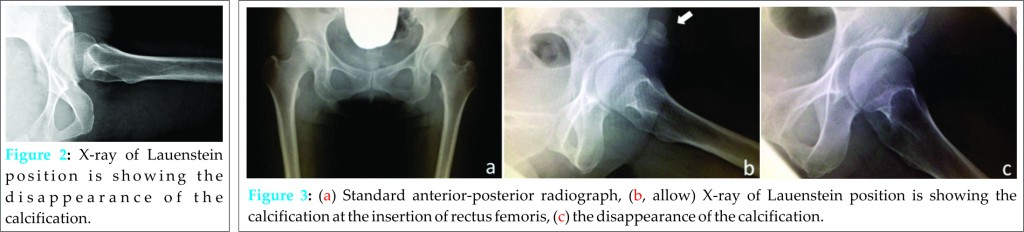

Oral non-steroidal anti-inflammatory drugs (NSAIDs: 180 mg of loxoprofen sodium hydrate per day) was administered. The pain was gradually relieved. At 1-week after her first consultation, VAS was 3. At 4 weeks after her first visit, VAS was 0, and radiographic examination showed disappearance of the calcification. At 6 months follow-up, there were no symptoms and no recurrence of the calcification (Fig. 2).

A 40-year-old female woman presented to our clinic following a 2 weeks episode of intermittent severe right hip pain (rated 9/10 on VAS), which was relieved by taking oral NSAIDs, clinically active hip flexion was restricted. Radiographic examination revealed the calcification at the inferior, anterior iliac spine (Fig. 3). Because she had severe pain regardless of taking NSAIDs, 3 ml of 1% xylocaine and 1.65 mg of methylprednisolone were injected into the inferior, anterior iliac spine. After 1-week the injection VAS became 0 and no restriction of hip motion was observed. Standard radiography after 8 weeks revealed complete absorption of the calcification (Fig. 3). Clinical review 1-year after her injection showed no reoccurrence of her symptoms.